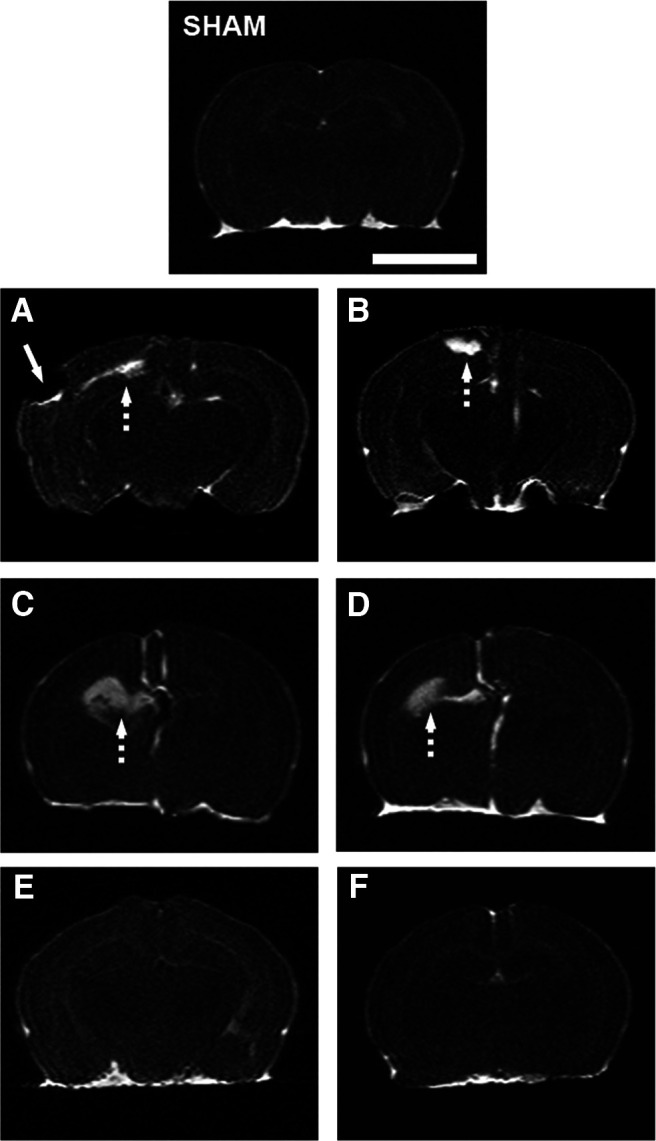

Rats exposed to hypoxia-ischemia had detectable lesion volumes of ∼25% at P14 and P37. At P14, the only treatment that significantly reduced the lesion volume was CBD 1 mg/kg combined with HT (Fig. 7). At P37, animals treated with CBD 1 mg/kg significantly decreased the volume of lesion. Combination of CBD 1 mg/kg with HT resulted in significantly superior effects compared with HT alone (Fig. 7). Representative images of all groups at this developmental age are included in Figure 8.

At P14, the brain damage volume assessed by MRI was similar in VEH and CBD groups, while it was reduced in CBD-treated animals at P37. This difference between P14 and P37 is likely because hyperintense areas in T2WI shortly after hypoxia-ischemia correspond to areas of brain edema, including necrotic tissue and injured but recoverable tissue, the so-called “penumbral” area (ref. Fernández-López et al., 2007). CBD exerted a protective effect on brain tissue surrounding the cortical infarcted area at P14, showed by histologic and Western blot results. These findings suggest that CBD administration recovers the penumbral area, preventing necrosis and reducing the damage in the neonatal HI model, as previously shown in other neonatal models (ref. Lafuente et al., 2011; ref. 2016; ref. Ceprián et al., 2017; ref. Barata et al., 2019). The final reductions of brain damage volume and neuropathological score by CBD were greater than hypothermia alone.